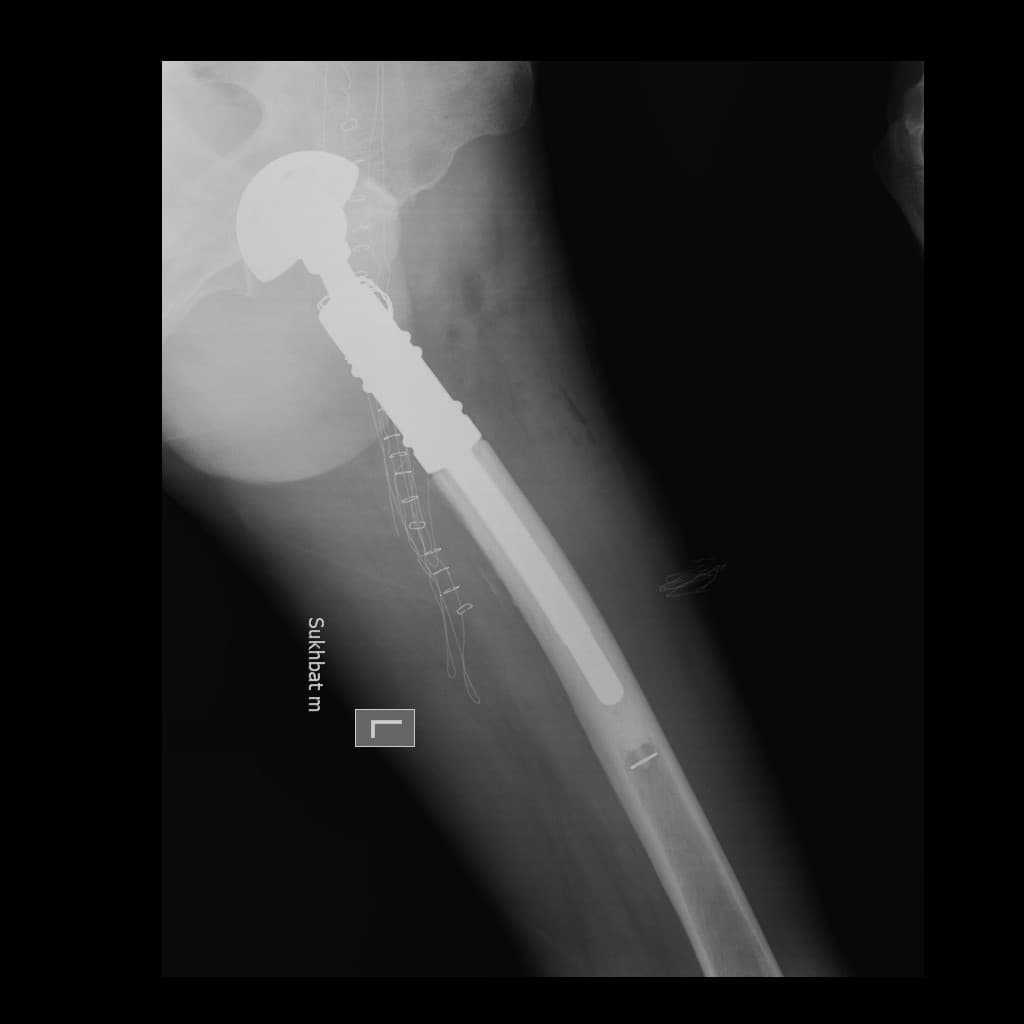

Түнхний үений төрөлхийн мултрал дутуу хөгжилтэй өвчтөний мэс заслын өмнөх болон дараах рентген зураг

Түнхний үе бүтэн солих мэс засал (THA) image3Түнхний үе бүтэн солих мэс засал (THA) image4